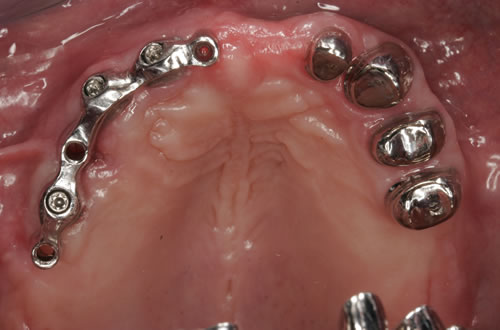

Abb. 3.7: Individuelle Stegversorgung aus Stahl auf vier Implantaten im zahnlosen Unterkiefer.

Abb. 3.8: Individuelle Stegversorgung aus Gold auf vier Implantaten im zahnlosen Unterkiefer.

Für den zahnlosen Ober- und Unterkiefer werden dies häufiger Stegkonstruktionen oder Teleskopversorgungen sein (Abb. 8.8 bis 8.16).